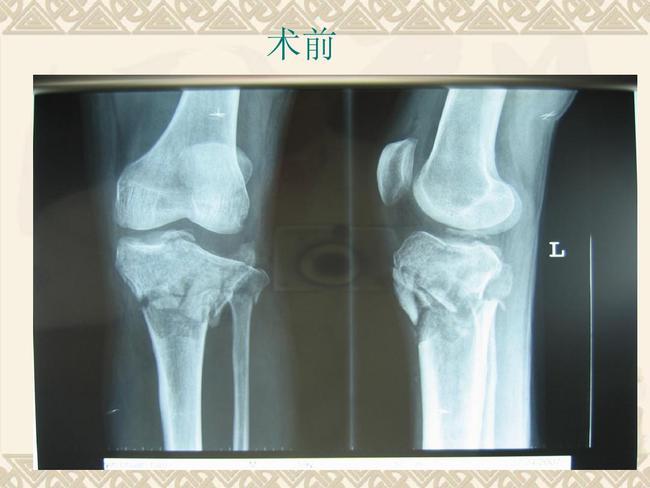

胫骨内侧髁骨折

胫骨内侧髁骨折,胫骨内侧髁骨折图片

检查部位:dr膝关节正侧位(左) 所见:左胫骨平台髁间嵴骨折复查:胫骨

胫骨髁间嵴骨折一例

胫骨内侧髁骨折图片

胫骨髁骨折图片

胫骨髁间骨折图片